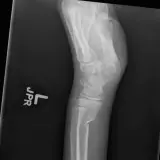

Over 2,100 interactive radiology cases, curated by radiologists for your level of training. Scroll, window, and view cases full screen — just like on PACS. Click linked findings in each writeup to jump straight to them on the image. Cases include sample reports, a focused discussion section, original illustrations, and videos.

Des cas entièrement interactifs avec les outils attendus d'un PACS — défilement, fenêtrage, zoom, déplacement, mesures, ROI et mode plein écran.

Des annotations détaillées mettent en évidence les résultats clés directement sur les cas. Cliquez sur les résultats liés dans les descriptions de cas pour accéder à leur emplacement exact sur l'examen.